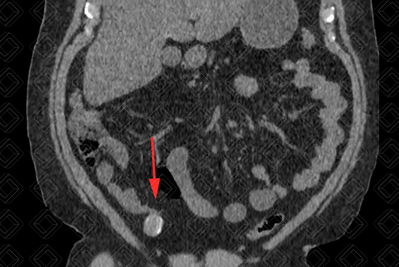

Texto alternativo para a imagem Figuras 1 e 2. Créditos: Dra. Elazir Mota - Rio de Janeiro/RJ

Descrição das figuras 1 e 2: Tomografia computadorizada do abdome; cortes sagital e coronal evidenciando imagem tubular, hipodensa e com calcificação parietal (setas vermelhas), compatível com mucocele de apêndice.

• Tomografia computadorizada do abdome: Em geral, vemos uma lesão tubular, hipodensa, contígua a base do ceco e, em cerca de 50% dos casos, elas contêm calcificações murais (figuras acima). Atenção: Diante da presença de espessamento parietal irregular e nódulos murais, devemos suspeitar de malignidade. Por isso, o exame idealmente deve ser realizado com contraste venoso;